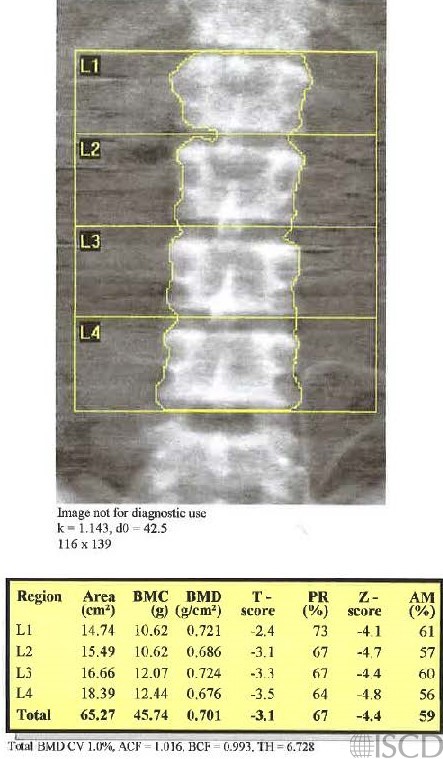

This is the same patient scanned without the presence of peritoneal dialysate.

The left panel shows a Hologic lumbar spine DXA with indwelling dialysate and the right-hand panel shows the same patient after the dialysate was drained. Notice that the spine BMD increases after the dialysate is drained. The TH, or thickness value, also decreases after the dialysate is drained.

Ascites and indwelling peritoneal dialysate may not produce a visual artifact on a DXA scan. It is important that a DXA technologist interview the patient and ask questions about the possible presence of ascites and peritoneal dialysate. The presence of indwelling peritoneal dialysate has been found to significantly lower spine BMD, and it is recommended that patients should be scanned without indwelling dialysate (Mann et al.). The presence of ascites generally decreases BMD At the lumbar spine (Guanabens et al. and Labio et al.). The precision of a bone density measurement would be affected if a patient is scanned at one time with dialysate or ascites and the next time without dialysate or the presence of ascites.